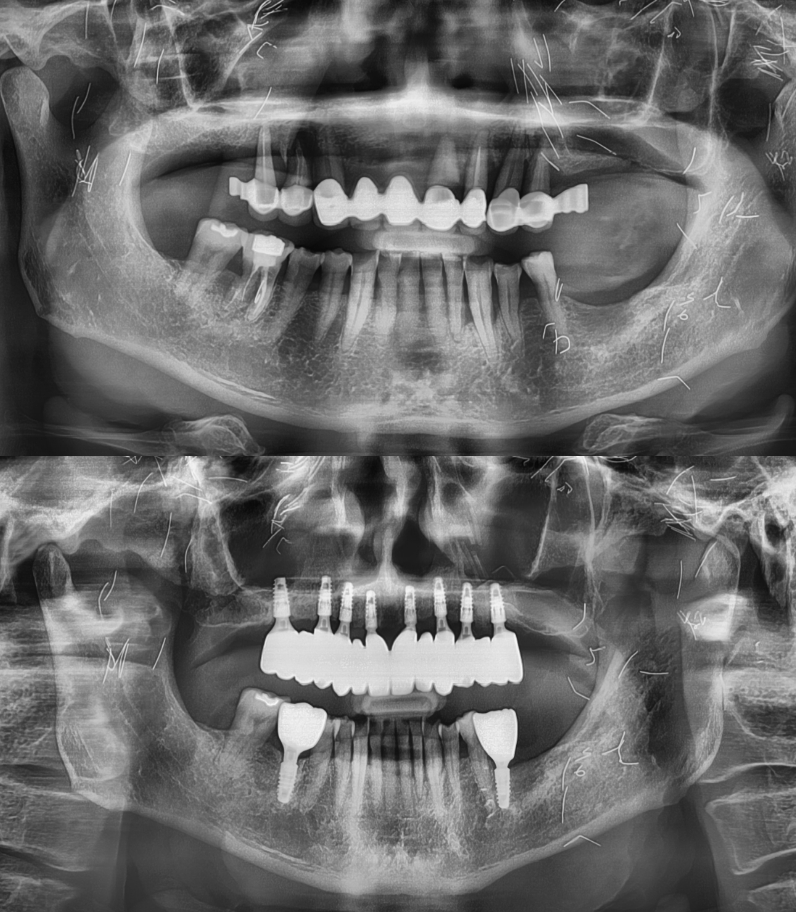

임플란트 전/후

실제 케이스

성공적인 임플란트 치료는 세밀한 분석과

그에 맞는 치료가 중요하기에

다수의 치료 경험을

보유한 의료진이 상주한 곳에서 시작하시기 바랍니다.

임플란트

환자 성함 : 권**

치료기간 : 2023.06 - 2024.07 (1년 1개월)